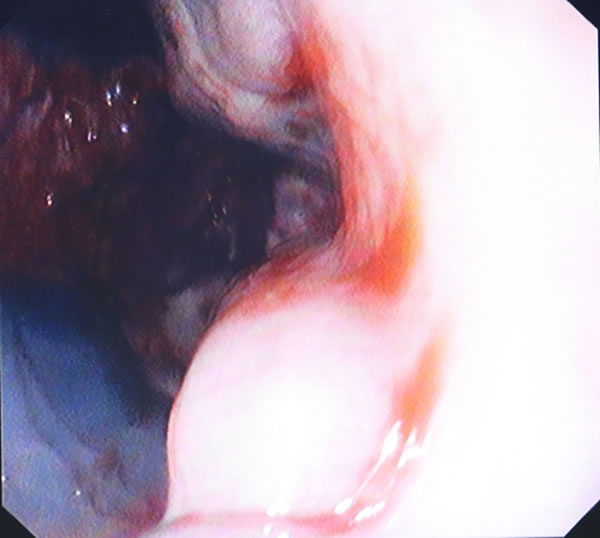

郎溪县人民医院成功开展了胃镜下食管静脉曲张硬化术

郎溪县人民医院消化内科与南京中大医院协作,成功开展了胃镜下食管静脉曲张硬化术。该技术适用于肝硬化合并食管静脉曲张破裂出血及预防再出血患者,减少患者反复出血带来的痛苦,提高生存质量。